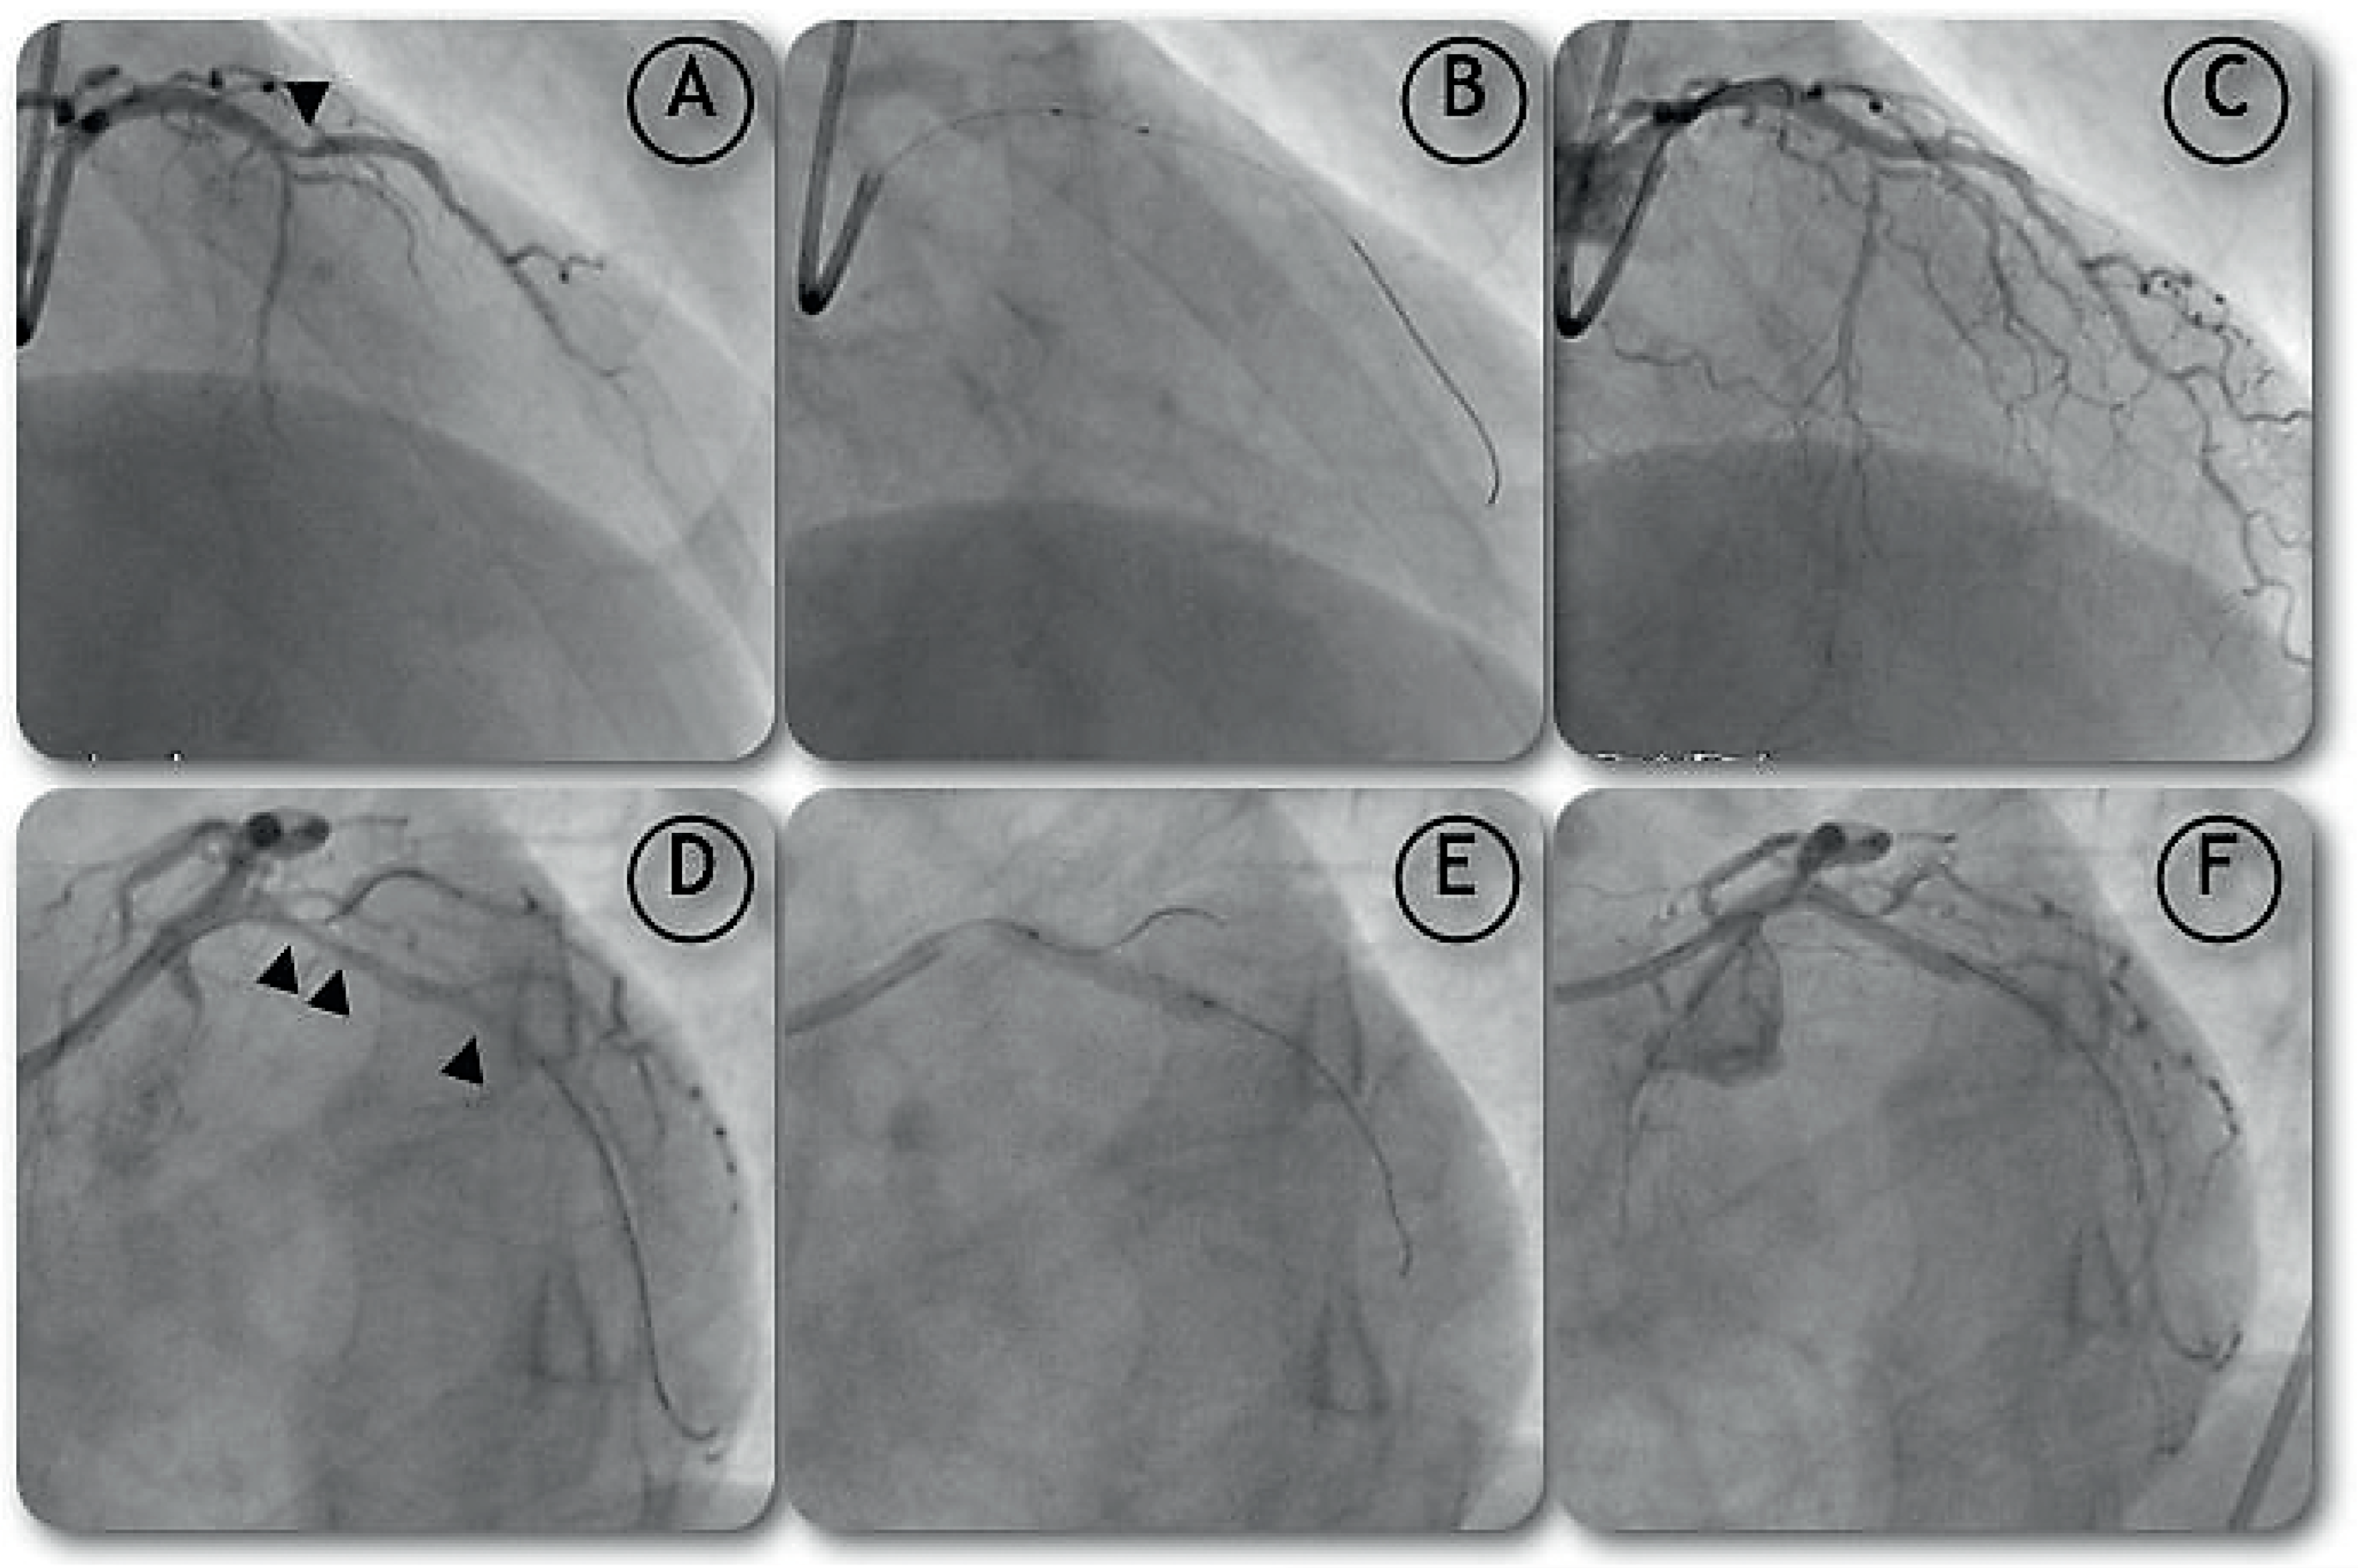

Case report